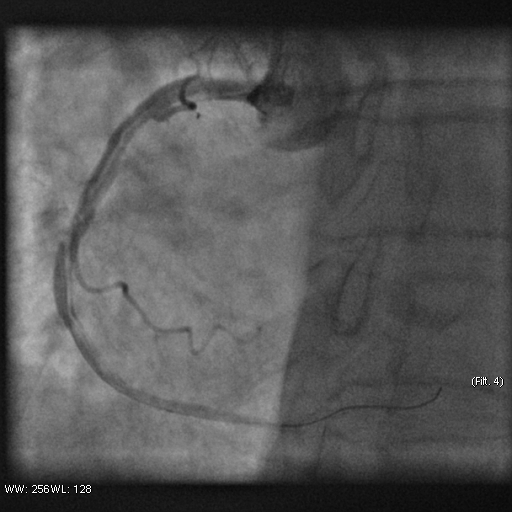

Stenosis of the anterior interventricular artery in the 6.7 segment is 95%. Stenosis of the orifice of the diagonal artery of the 1st order is 95%. Stenosis of the circumflex artery in the 13th segment is 40%. During coronary angiography, pronounced spasm is noted in the 2nd segment of the right coronary artery with complete occlusion of the artery lumen. After stopping the spasm, coronary angiography shows a spiral (spontaneous) dissection of the right coronary artery from segments 1 to 3.

A guiding catheter JR 3.5 6Fr was inserted along a 0.035" 260.0 cm guidewire. The guidewire was removed. The right coronary artery was catheterized. A 7Fr Y-click connector (complete with an insertion device and a guidewire rotation device) was connected to the guiding catheter. A coronary guidewire Whisper ES 0.014" 190 cm, Asahi Gaia Third 0.014" 190 cm was inserted and brought into the orifice of the right coronary artery. The guidewire was inserted beyond the lesion zone of the right coronary artery in segment 2, then into the distal sections. Wilma NC 2.00*20.0 mm and Wilma NC 3.00*15.0 mm balloon catheters were inserted alternately along the coronary guidewire - predilation of the lesion zone of the right coronary artery in segment 2 was performed. Inflation of balloon catheters 14 atm. with an inflator, the balloon catheters are deflated and removed. A stent is inserted along the coronary guidewire - the Yukon Chrom PC 3.0 * 28.0 mm system, Yukon Chrom PC 3.0 * 28.0 mm, Cid Cre 8 3.50 * 25.0 mm, Cid Cre 8 4.0 * 16.0 mm - the stent is implanted in the lesion area of the right coronary artery in the 2nd segment. Inflation of the balloon catheter 9-16 atm. with an inflator, the balloon catheter is deflated and removed. Control coronary angiography - blood flow in the stenting zone is TIMI3, there are no signs of dissection or stent dislocation.